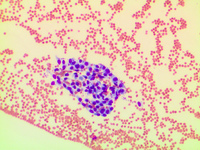

Endothelial cells 1

A custer of cohesive endothelial cells is seen on peripheral smear in a sheath like conformation. The cells have abundant homogenous cytoplasm and eccentric round nuclei with condensed chromatin. Adhesion of many platelets to these cells is seen. There is no features of atypia or reactivity.